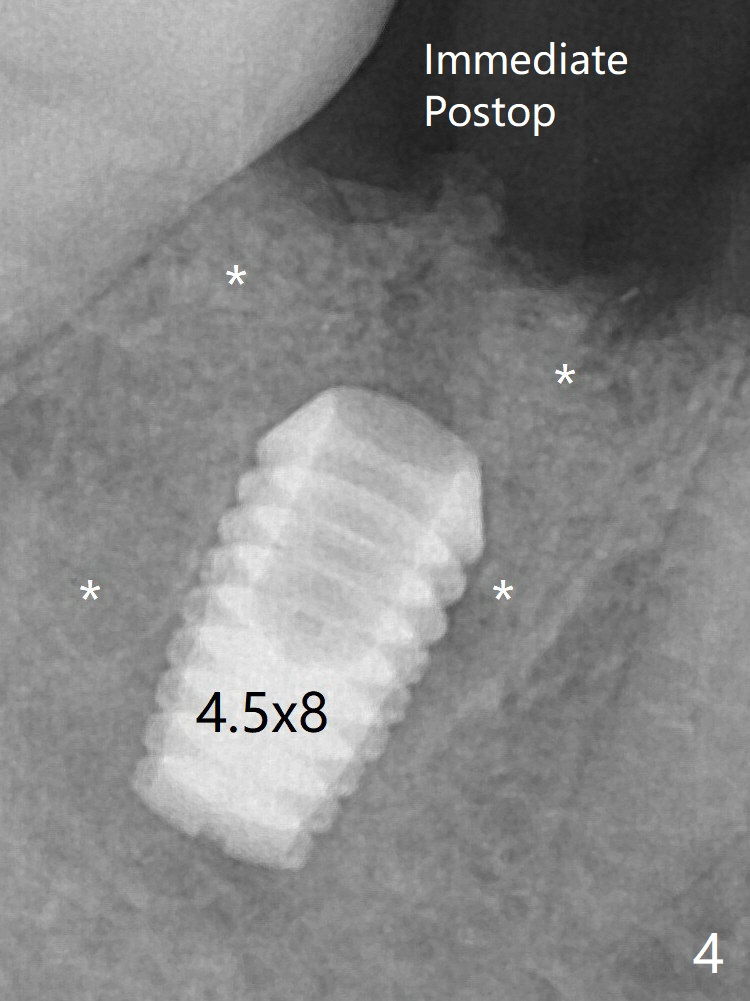

Following 4.5x11.5 mm drill, a 4.5x8 mm Bicon implant is pressed fit; its stability is lightly enhanced with placement of sticky bone in the remaining sockets (Fig.4 *) and around the black plug (Fig.5 P). The implant appears to remain covered by the bone 3 months postop (Fig.11 (* socket shield)). Cortical bone starts to form crestal 7 months postop (Fig.12 arrowheads, coronavirus).